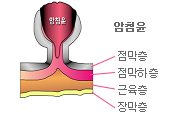

| 18 | 위내시경 | 검진동 3층 | 약 10분 | 식도질환, 위염, 위궤양, 십이지장 궤양, 위암, 헬리코박터파이로리균검사 등 |       |

| 19 | 대장내시경 | 검진동 3층 | 약 20~30분 | 대장의 염증, 궤양,

용종, 암

(특히 조기암 발견) 등 |